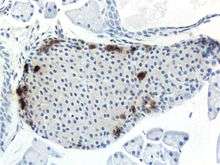

Mouse islet immunostained for pancreatic polypeptide

Mouse islet immunostained for pancreatic polypeptide Mouse islet immunostained for insulin